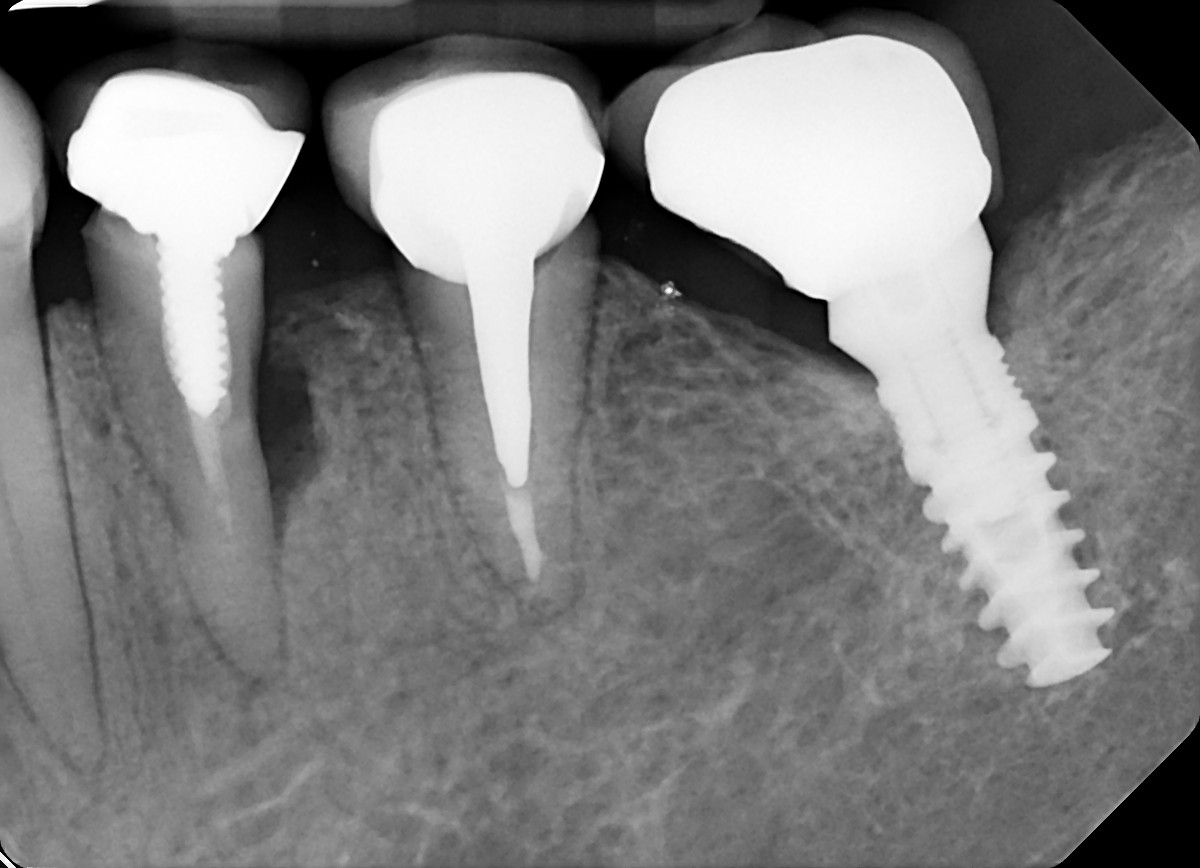

22. What option can be selected for the crown over the implant?

25. What option can be selected for the crown over the implant?

28. What option can be selected for the crown over posterior implant?